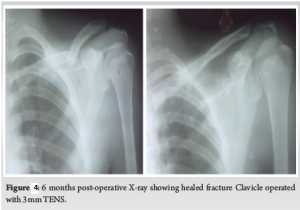

52 (55.32%) out of 94 patients were treated by conservative methods, and 42 (44.68%) were treated by surgical intervention. In that 15 (15.96%) patients were treated by ORIF or closed reduction and internal fixation with titanium elastic intramedullary nail. Notably, 2 cases of fractures treated with TENS required open reduction due to inadequate alignment and difficult closed reduction (Fig. 1). 27(28.72%) cases were treated by ORIF with 3.5 mm plate and screws. The mean follow-up was 8.2 months, ranging from 6 to 13 months. One of our cases of clavicle fracture operated by closed TENS, showed good fracture healing at 6 months (Fig. 2).

It took a mean of 4.9 weeks for union with middle third fractures and mean of 5.8 weeks for fractures of the lateral third treated by conservative methods (Fig. 3). The duration of immobilization ranged from 4–8 weeks (Mean – 5 weeks) till clinical union.